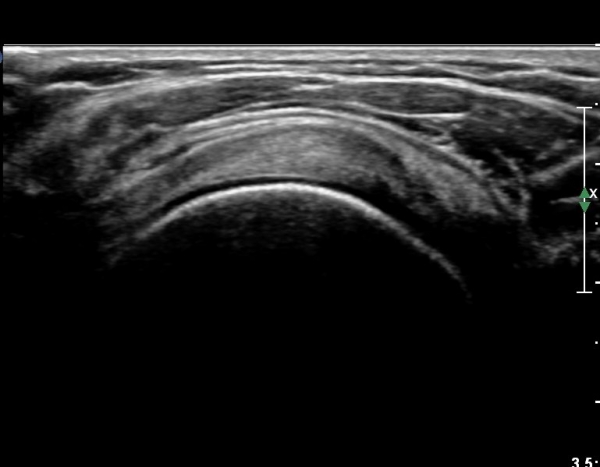

ÃÊÀ½ÆÄ ¼Ò°ß :  ±Ø»ó°Ç Á¾´Ü¸é°Ë»ç¿Í Ⱦ´Ü¸é°Ë»ç»ó ƯÀÌ ¼Ò°ß º¸ÀÌÁö ¾ÊÀ½(»çÁø 1, 2).